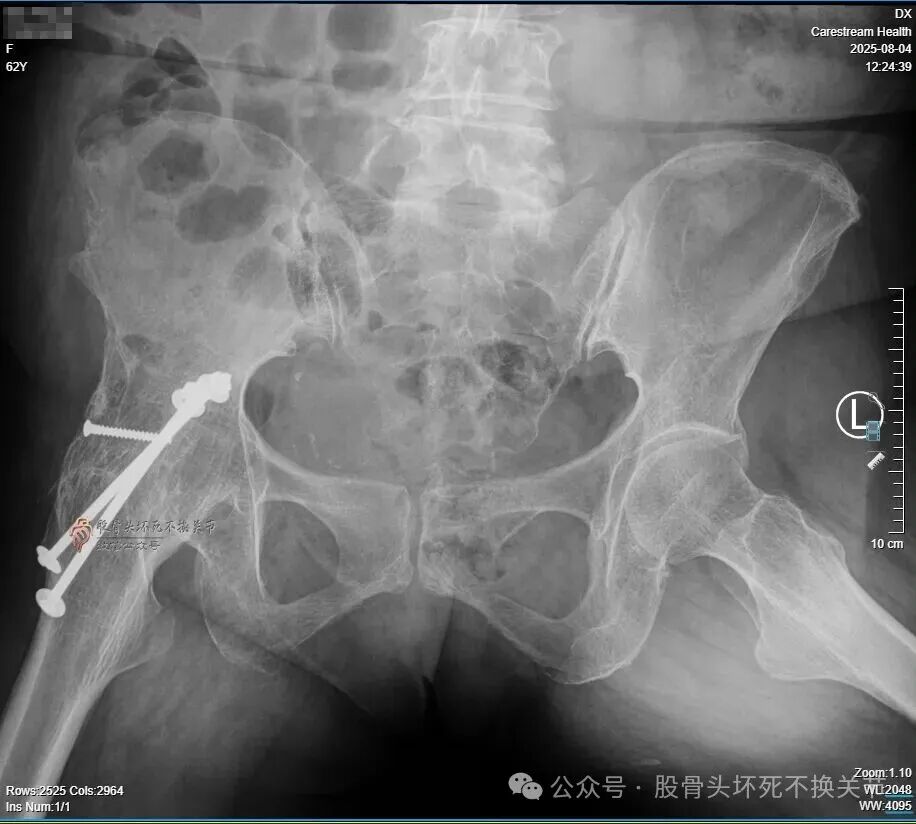

前段时间咱们提过一位62岁的病人,21年前因“右侧股骨头坏死”行右髋关节融合手术,近期要求行关节置换手术。在医生圈反响很大,现将结果汇报给如下。

髋关节骨性融合20余年,进行关节置换必须完全取出内固定,否则髋臼假体的安装就无法实现;残存内固定轻则影响假体安装,重则造成血管神经损伤,甚至危及生命。

之前采用的是金属螺栓固定,且螺母在髋臼内壁,所以不能存留任何内固定,即便取不出来,臼底就是开窗也要拿出来,但那样做无疑创伤非常大、危险也随之而来。

而后来证实,20多年前还真是一个主打不锈钢的年代,的确是全套不锈钢——想想都后怕!